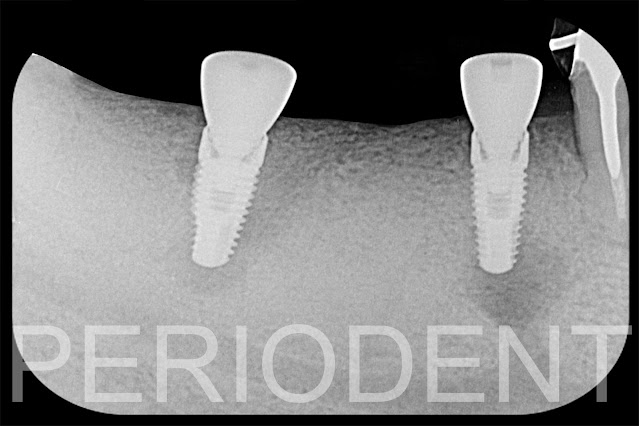

15. 製作植牙手術導版,電腦斷層影像

16. 補骨後九個月進行植牙